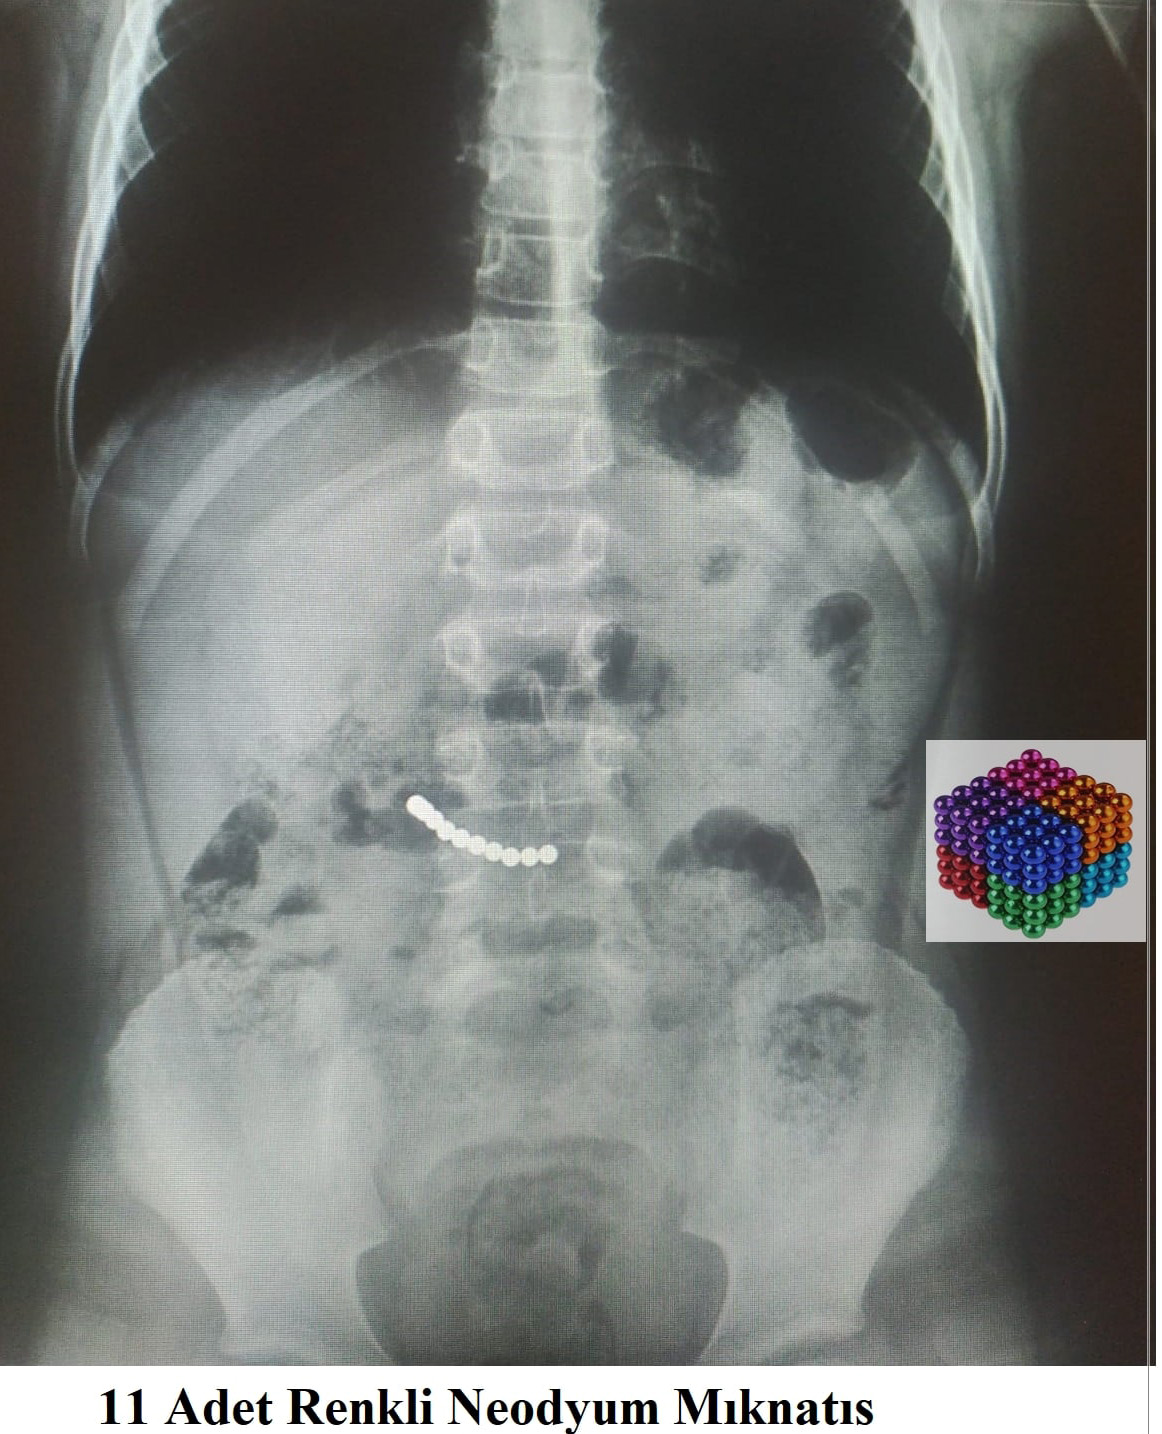

7 yaşındaki çocuğun midesinden 11 mıknatıs çıktı